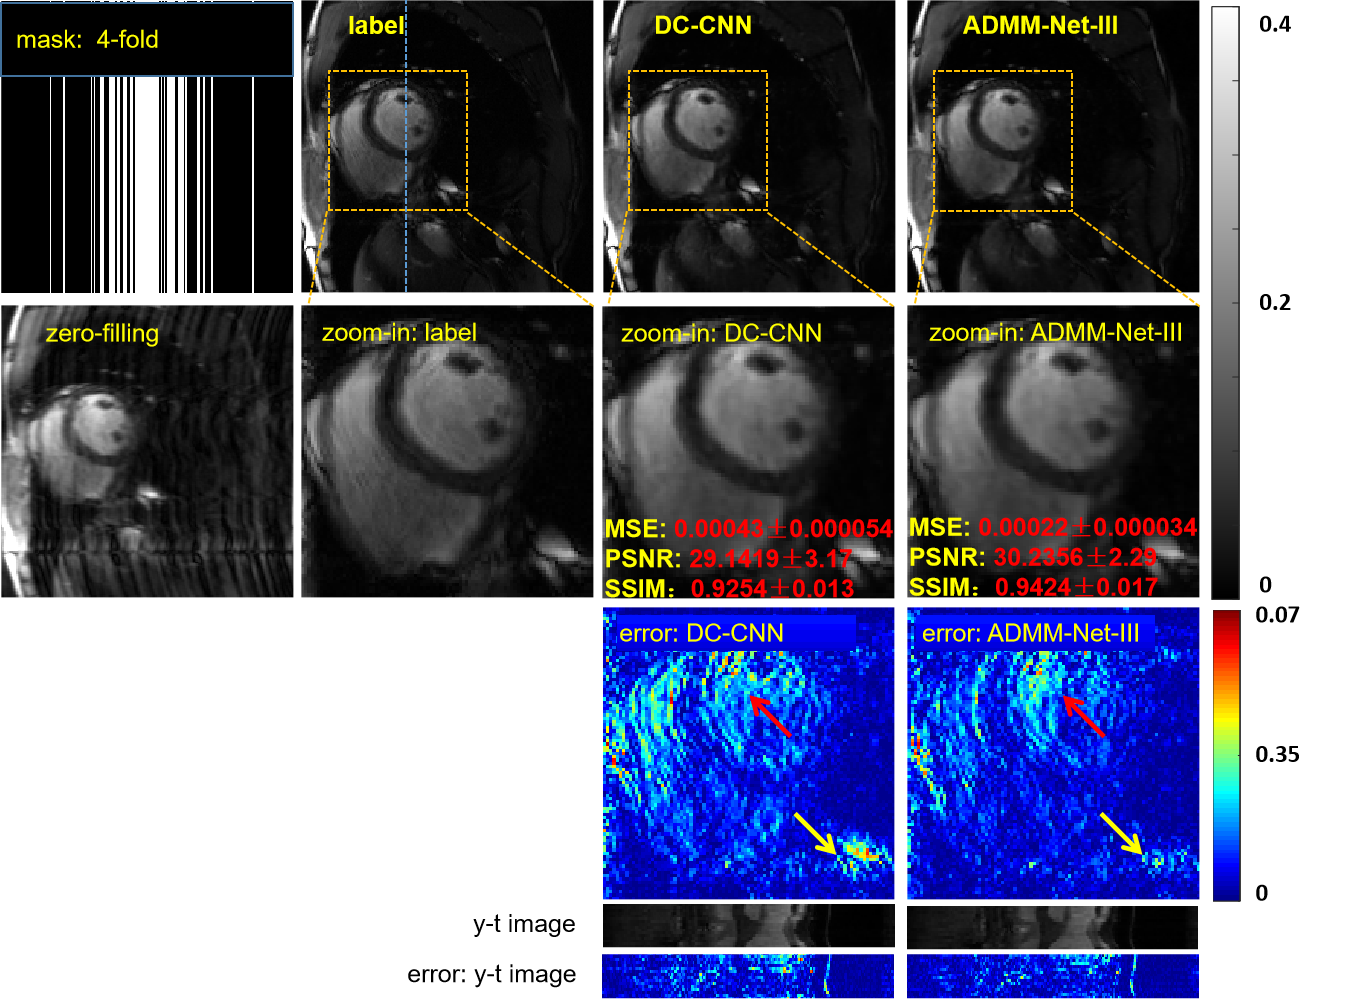

Although we introduced the proposed parallel network in Section II.C, where ADMM-Net-III was selected as the reconstruction network, the full unsupervised framework is not limited to this specific reconstruction network. The reason we chose ADMM-Net-III is that it is a deep learning model-based unrolling method, which requires less data than do vanilla end-to-end methods and usually exhibits superior reconstruction performance compared to other methods. In this section, we compared the reconstruction results of ADMM-Net-III with those of DC-CNN [22], which is a state-of-the-art deep learning method for dynamic MRI. We focused on a D5C5 model, which works well for the DC-CNN model and consists of five blocks (C5), each of which contains five convolutional layers (D5). We trained two models under the proposed unsupervised framework. The configuration parameters of the network remain unchanged. The only difference was that one reconstruction network used ADMM-Net-III and the other used D5C5. The two models had similar numbers of learned parameters: ADMM-Net-III had 762k parameters and D5C5 had 776k parameters. The reconstruction results are shown in Fig.8. Both the qualitative and quantitative results have consistent observations: the coil reconstruction network using the ADMM-Net-III model has somewhat smaller artifacts and more details, especially in the heart region (as indicatd by the red and yellow arrows in the error maps). To create clearer comparisons, the display range was narrowed to [0, 0.07].